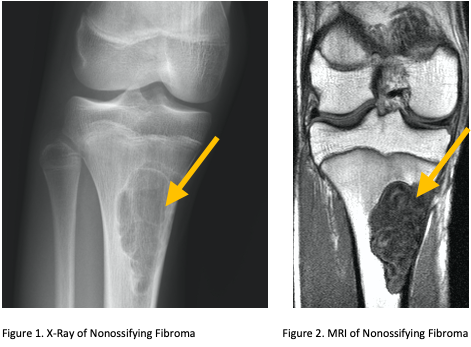

- • Imaging includes X-rays, MRI, CT and PET Scans may also be used as well as bone scans.

Radiographic imaging is used to help form a diagnosis. These include X-Ray, MRI, CT and Bone Scans.

An example of a X-Ray and MRI are shown.